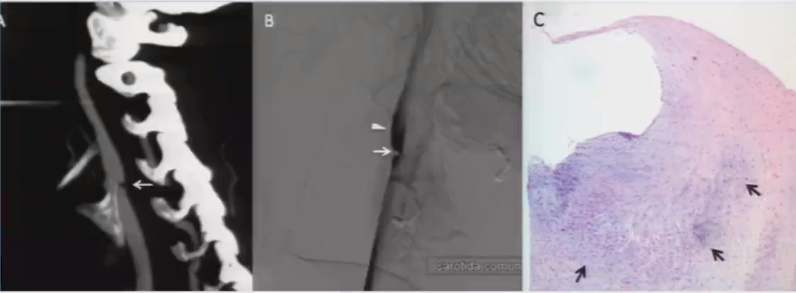

3. 颈动脉蹼(Carotid artery web)

➤ 动脉腔内隔膜状突出物(有时班瘤样扩张),多出现在颈动脉球部,为非典型的内膜下棘状细胞纤维增生物,不伴内皮的增生,无炎性细胞浸润,无脂质浸润;

➤ 多发生在颈动脉(颈动脉球附近),也可见于椎动脉;

➤ 引起血管狭窄;在蹼的远心面形成血流的滞留区,从而产生血栓;

➤ CTA上可见血管腔内充盈缺损,DSA上尚可见到造影剂滞留。

图3 颈动脉蹼

➤ 颈动脉蹼

图10